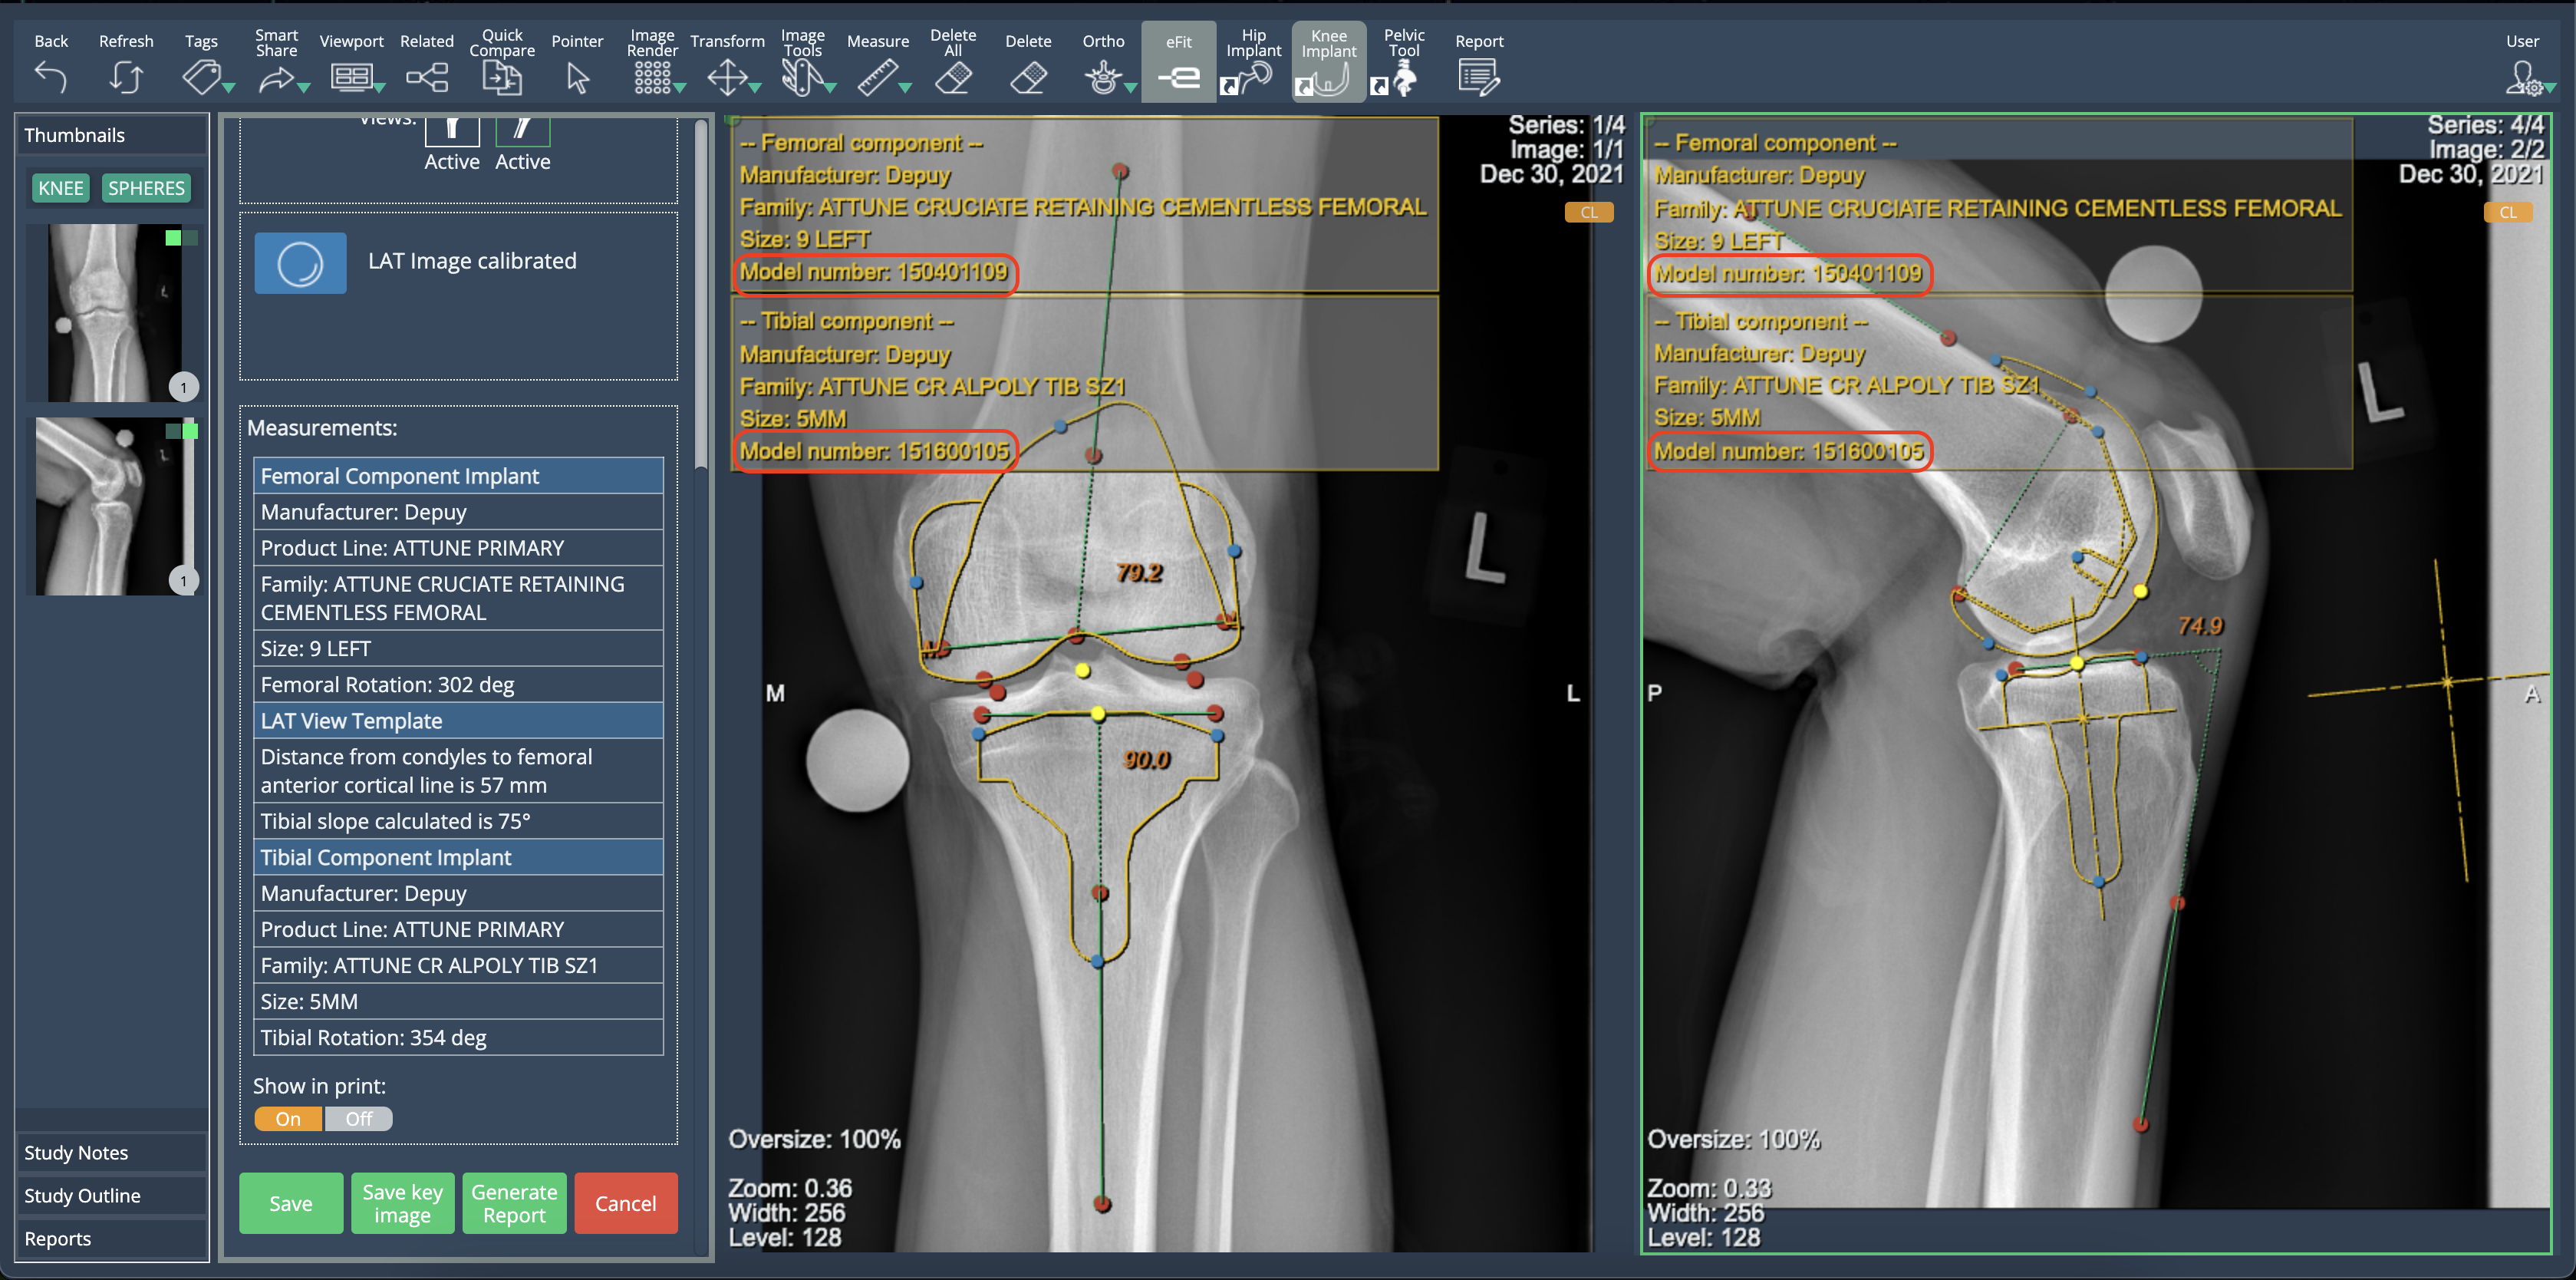

Implant Model Display in eFit

eFit now provides visibility of implant model information. When templating a hip or knee, the implant model number is displayed in the property list of each component. This information is available in the table shown when selecting "Show in Print", ensuring users have quick access to implant details.

Template Image Integration in eFit Reports

eFit reports now display images of the generated hip and knee templates. Previously, reports did not support image visualization. With this update, template images are automatically included, improving documentation and clarity.